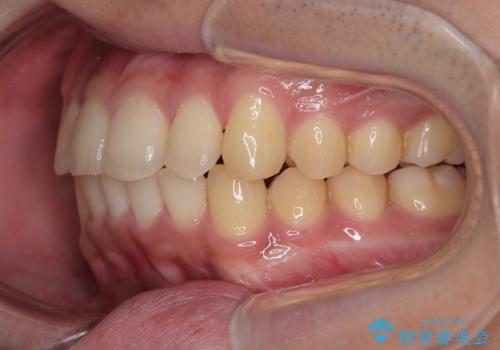

- 上下前歯の捻れやデコボコを気にして来院された患者様です。

マウスピース矯正でもワイヤー矯正でも対応可能でしたが、極力楽をして治したいとのことでワイヤー装置にて治療をおこなうこととしました。

口元はそれほど突出しておらず、患者様自身も気にしていらっしゃいませんでしたが、前歯の捻れやデコボコを解消すると、前方に拡大され、治療後に出っ歯仕上がりとなるリスクがあったため、補助装置により上顎臼歯を後方移動していくこととしました。

昼休みを活用して通院してくださり、1年半であっという間に終えることができました。